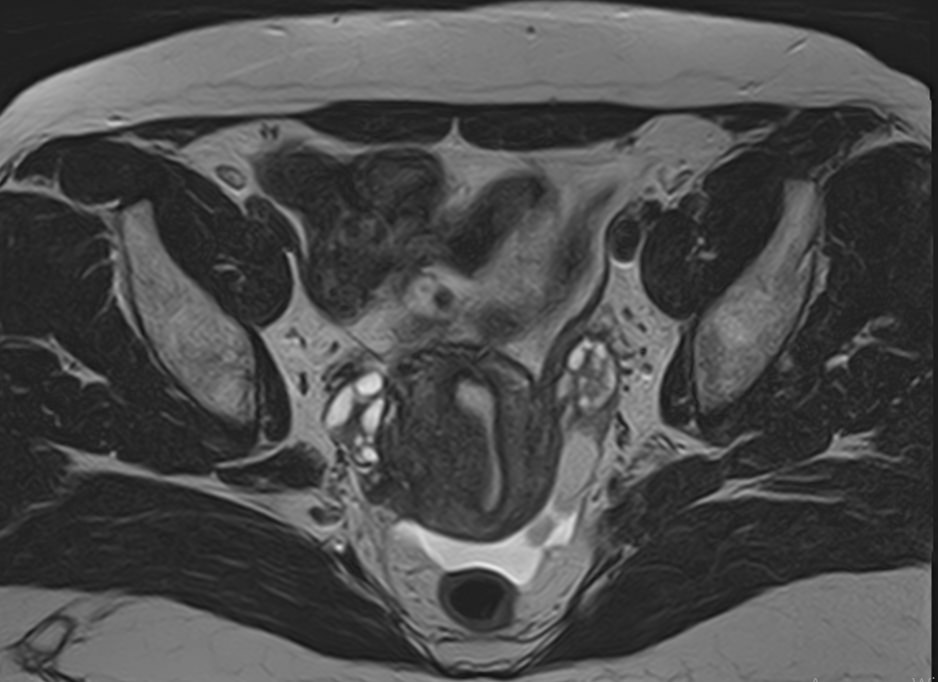

С помощью данного исследования можно получить детальное послойное изображение матки, яичников, мочевого пузыря и мочеотводящих путей, а также жировой клетчатки, окружающей органы, и лимфатических узлов.

• Эндометриоз и эндометриоидные кисты яичников;

• Изменение формы и положения матки (двурогая матка, патологический загиб матки, гипоплазия);

• Изменения в маточных трубах (кровоизлияния, новообразования и врождённые аномалии развития), яичниках и шейке матки;

• Миоматозные узлы, полипы и новообразования в матке;